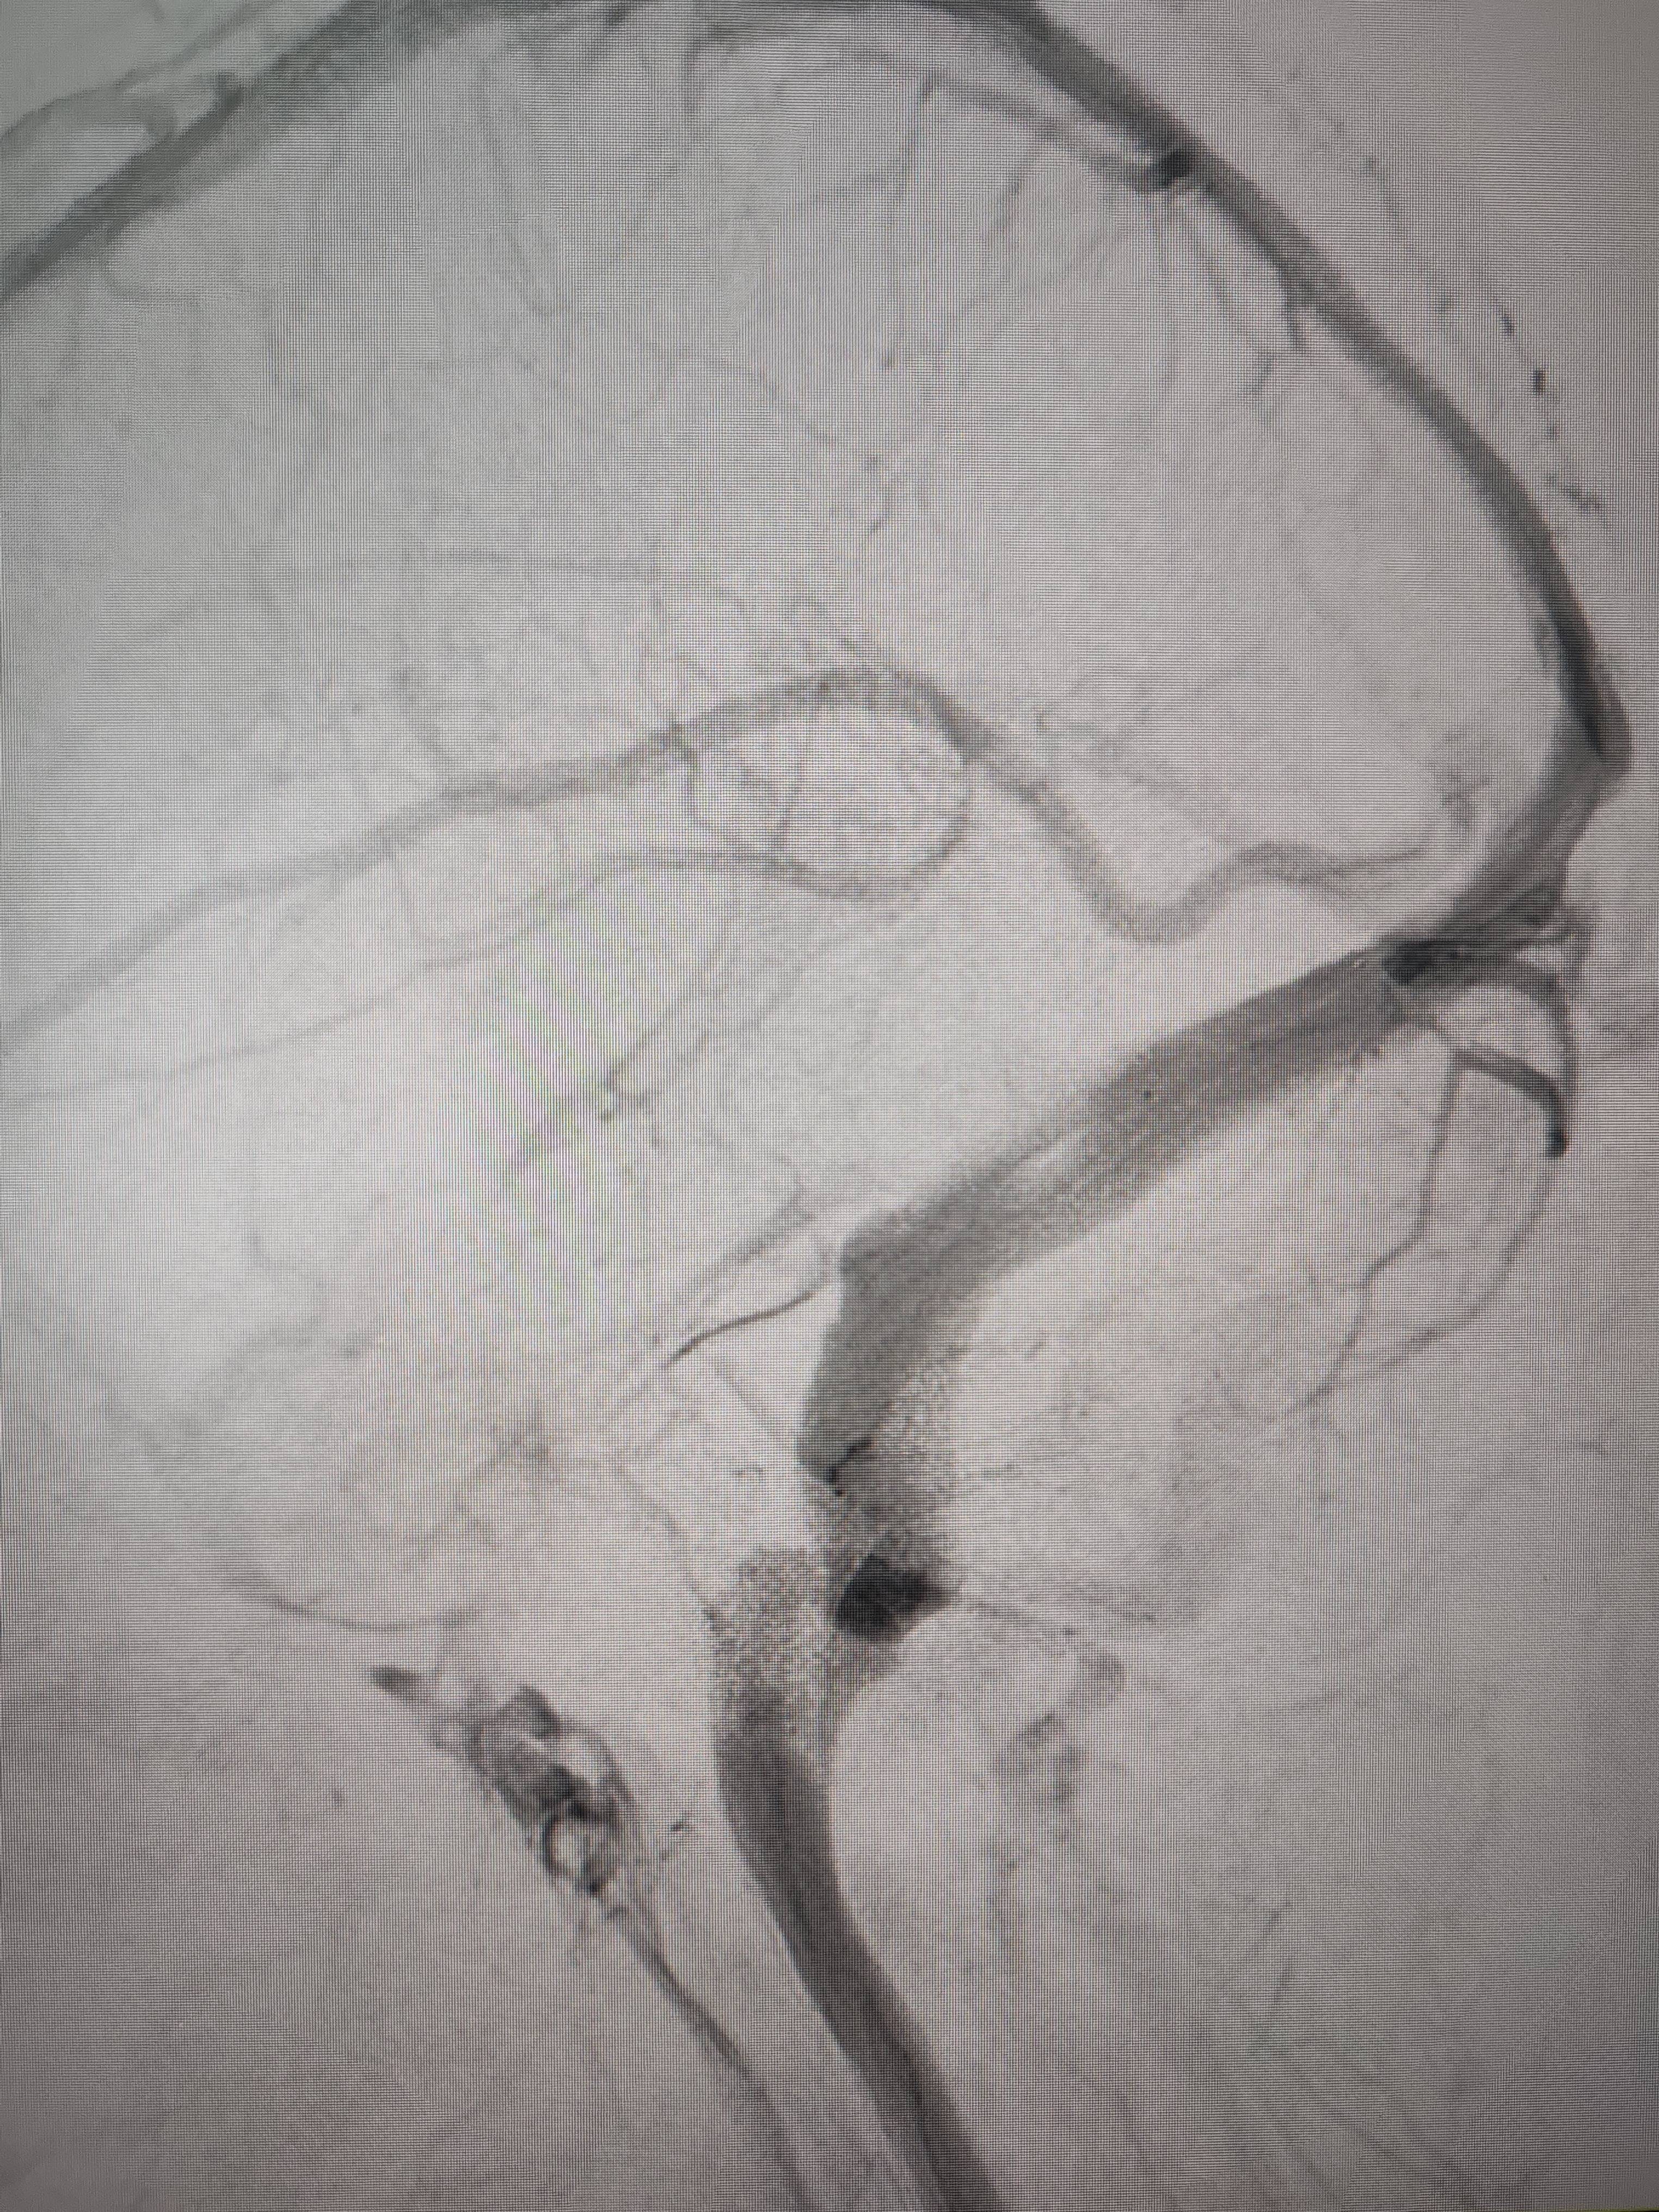

经过静脉窦支架置入手术治疗后,患者的静脉窦“堵点”被打通皇冠信用網出租足球。 南方+ 欧阳少伟 拍摄